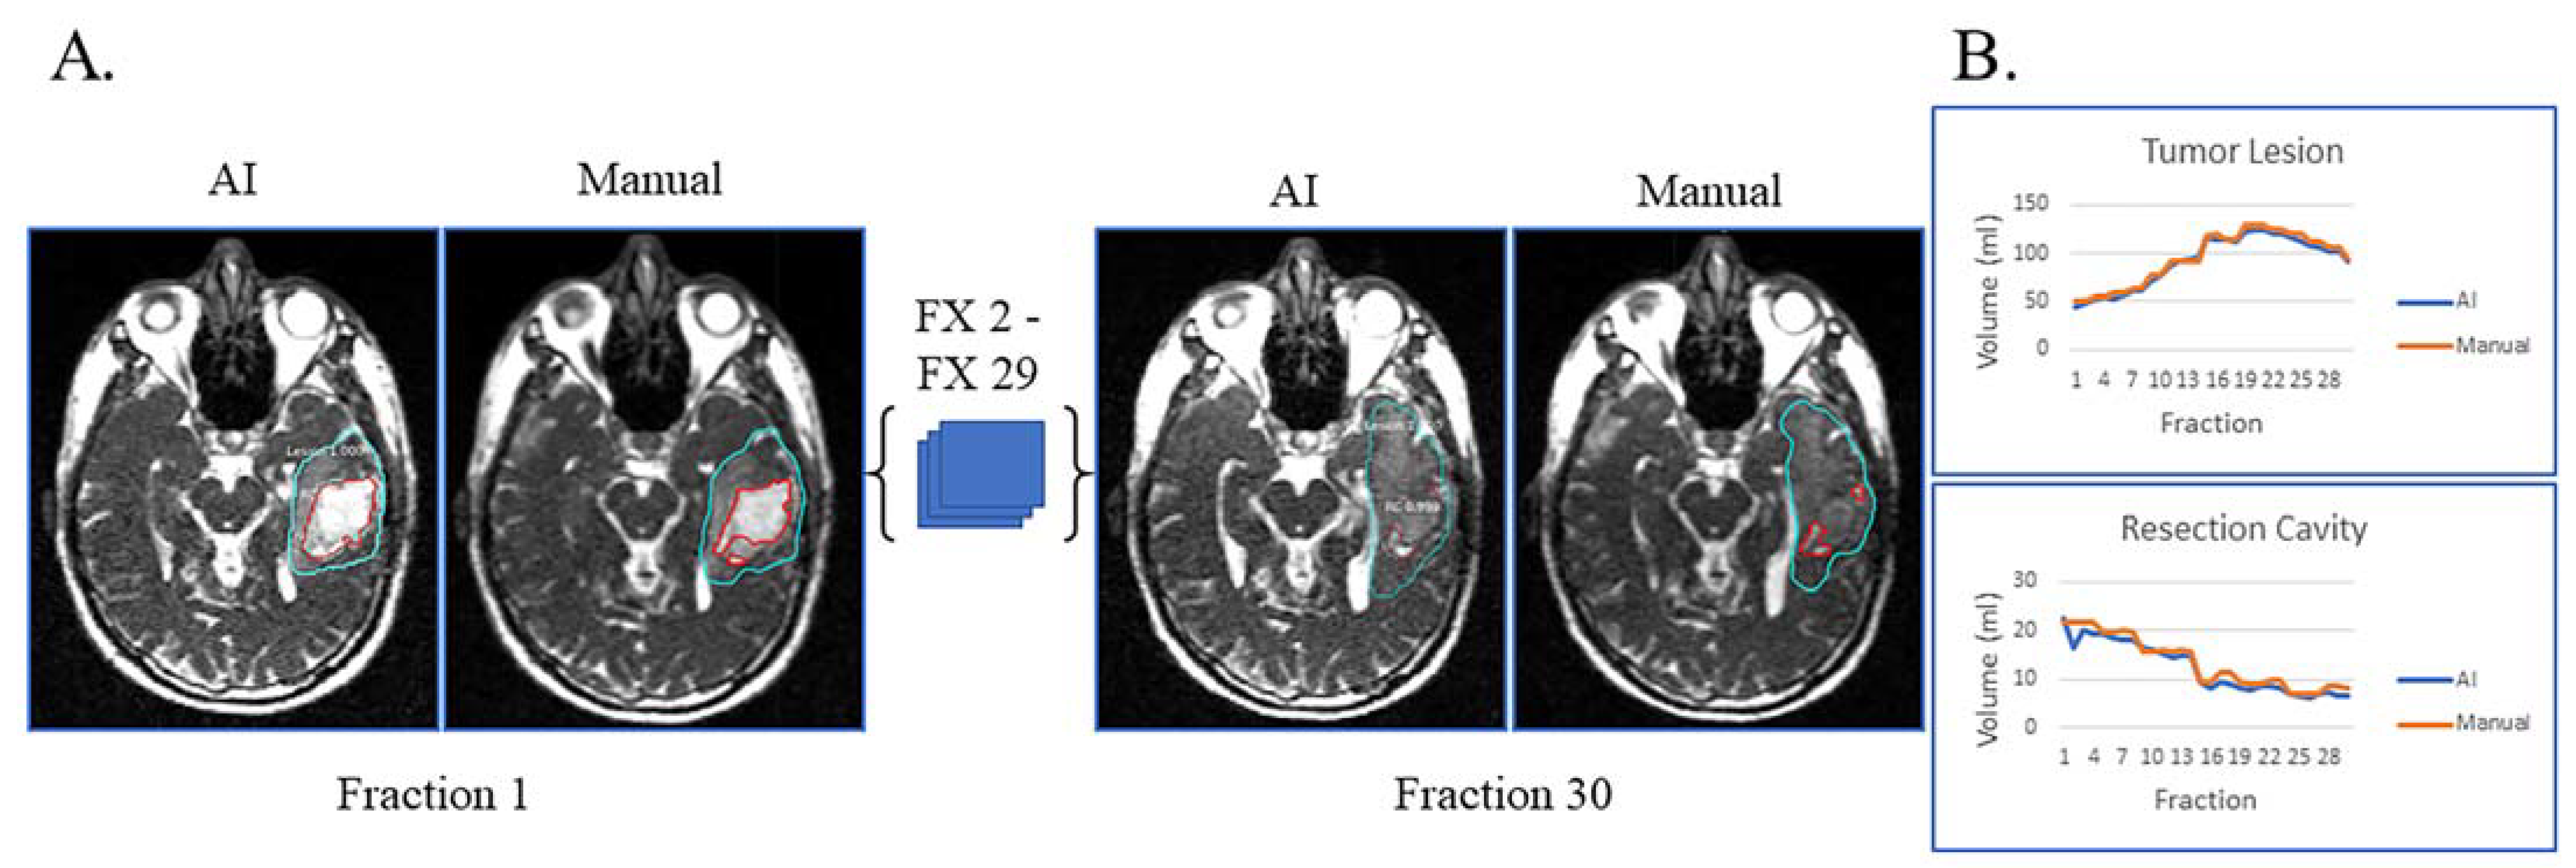

Figure 2A displays the automatic and manual contours of a patient with both resection cavity and tumor lesion after a sub-total resection. This patient had true progression, defined by tumor growth on high-field-MRI one month after the completion of RT with progressive worsening of disease on serial high-field MRI over the next six months that did not stabilize or improve. In addition to post-RT progression, this patient had progressive growth of their tumor during most of their treatment and mild resection cavity shrinkage. Of note, there is a volume decrease in tumor lesion volume starting around fraction 22, typically not seen with true progression (Figure 2B). However, this patient tapered off dexamethasone steroids prior to the beginning of RT but started back on dexamethasone around fraction 22 due to worsening symptoms, which could explain the decrease in tumor lesion volume seen towards the end of treatment. Despite this complexity, the AI-derived volumes over the 30 treatment fractions track closely with the manual ones for both resection cavity and tumor lesion.

Figure 2.

Sub-total resection with resection cavity and tumor lesion. True progression of tumor lesion was observed during the majority of treatment and later confirmed. A decrease in tumor lesion (likely edema) is seen towards the end of treatment when dexamethasone was started due to progressive headache. (A) Auto-segmentation (left) and manual (right) contours of tumor lesion (cyan) and resection cavity (red) at the first and last treatment fractions (FX) shown on MRI-linac bSSFP. (B) Volumes derived from AI (blue) and manual segmentation (orange) across treatment fractions for tumor lesion and resection cavity.